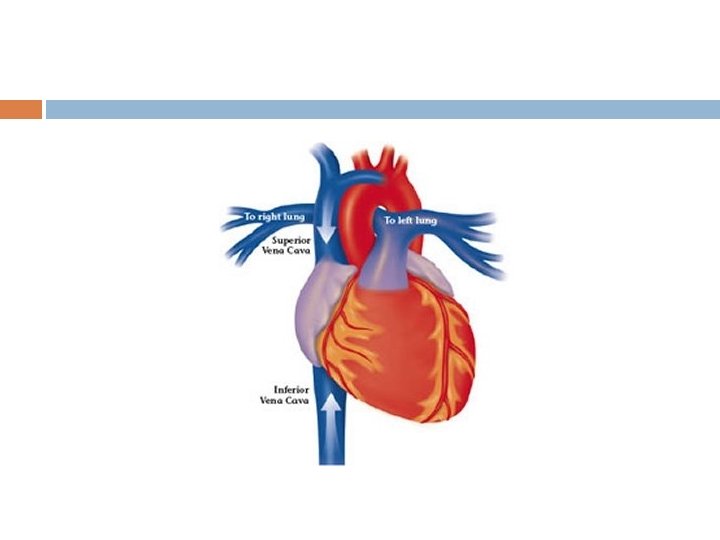

Superior & Inferior Vena Cava SVC: large vein that receives blood from upper body (head, neck, upper limbs) IVC: large vein that receives blood from the lower body (lower limbs, pelvis, abdomen) both return blood to right atrium